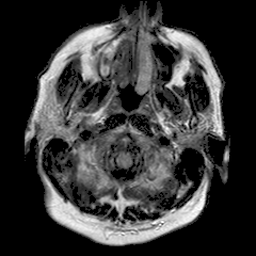

基于深度学习分割算法的 PyTorch 实现的 U-Net,用于脑部 MRI 中 FLAIR 异常区域的分割。该算法曾应用于论文《低级别胶质瘤基因组亚型与深度学习算法自动提取的形状特征之间的关联》(https://doi.org/10.1016/j.compbiomed.2019.05.002)。

模型

本仓库实现的分割模型是 U-Net,其架构如《低级别胶质瘤基因组亚型与深度学习算法自动提取的形状特征之间的关联》所述,并增加了批归一化层。

来自三家不同机构的验证病例的定性结果,DSC 分别为 94%、91% 和 89%。绿色轮廓表示真实标签,红色则为模型预测结果。图像显示的是预处理后的 FLAIR 模态。

随机选取的 10 个验证样本的 DSC 分布。红色竖线代表平均 DSC(91%),绿色竖线代表中位数 DSC(92%)。由于模型选择基于这些验证样本的平均 DSC,因此结果可能存在偏差。